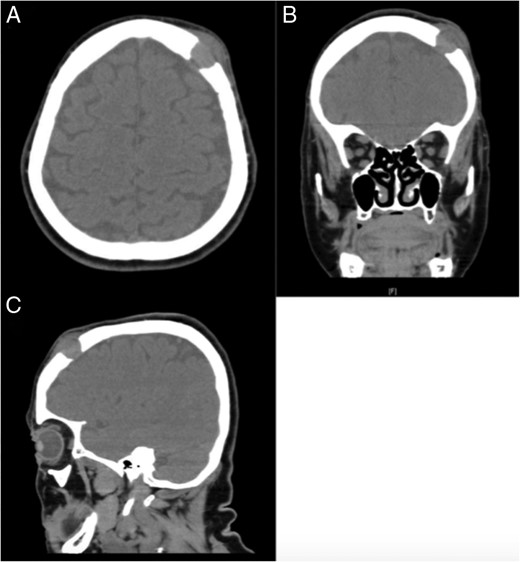

The patient, a 69-year-old white female, was referred by her primary care provider to a plastic surgeon at United Hospital Center for treatment of what was believed to be a soft-tissue mass of the left forehead (frontoparietal region) (Fig. 1). The mass had increased in size for the prior 2–3 months and resulted in a radiating pain down the left side of the face. The mass was non-mobile and tender to touch. Prior to this referral, the patient was relatively healthy with a past medical history significant for arthritis, depression and hypertension. Her surgical history was positive for tonsillectomy and partial hysterectomy. Her social history is significant for a 60-pack-year smoking history (1.5 packs/day for 40 years). The soft tissue mass had been managed conservatively for presumptive dermatological infection (subcutaneous/sebaceous cyst) with a 10-day course of levofloxacin 500 mg tablets taken once daily. The tablets, however, provided no symptomatic relief. Imaging (computed tomography (CT)) of the maxillofacial area and brain without contrast was obtained in addition to plain films of the skull. These images revealed a lytic lesion of the skull in the left frontopartietal region (Fig. 2). The patient was referred to the oncology department for further workup.

CT soft tissue demonstrating the presence of a lytic lesion in the left frontopartietal region. (A) Axial cut, (B) coronal cut and (C) sagittal cut.